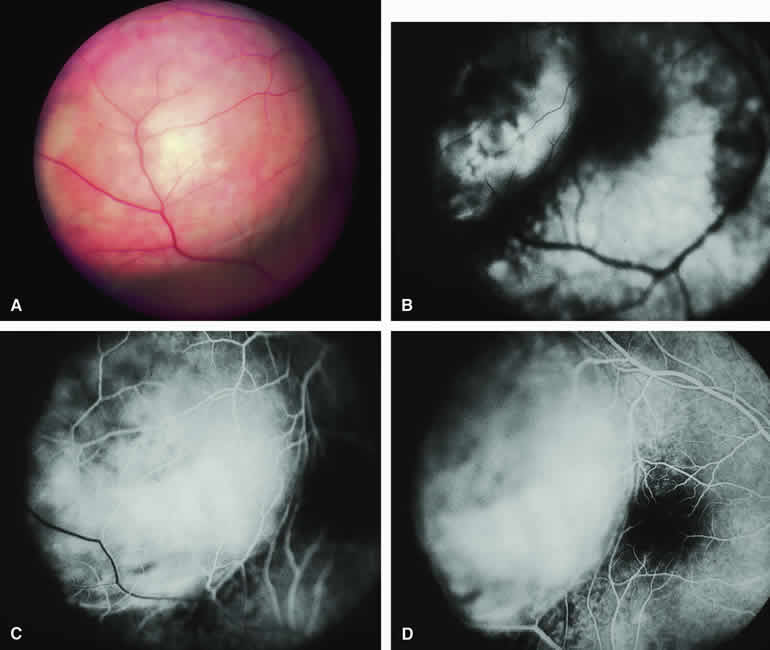

ICG angiography of a typical melanotic choroidal nevus (see Fig. 2) shows better definition of the basal area of the lesion than does fluorescein angiography. The entire lesion appears completely and uniformly dark throughout the ICG angiogram. Only the larger retinal blood vessels overlying the nevus are usually demonstrated on ICG angiography.